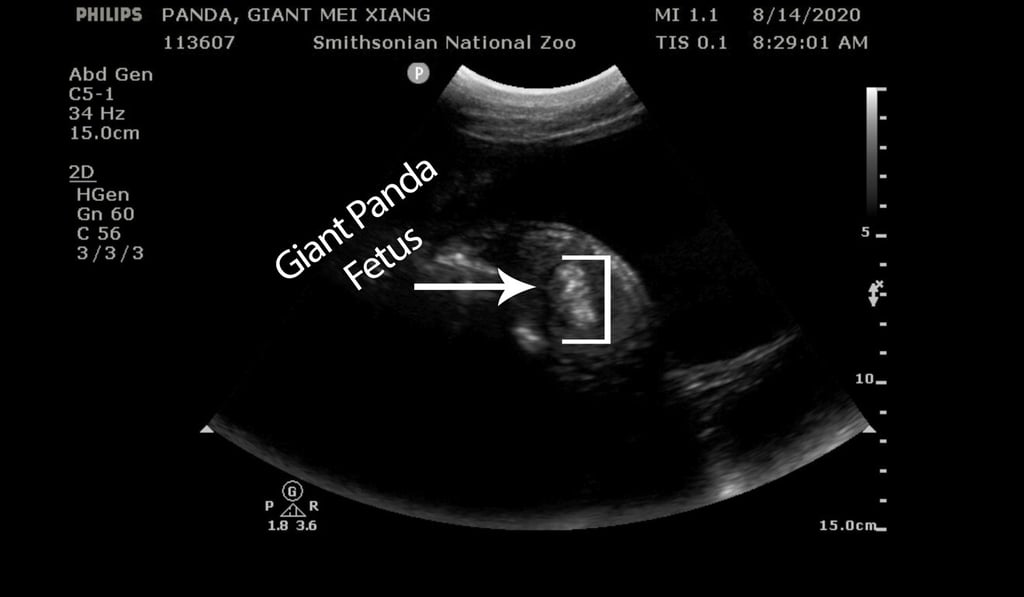

It said that veterinarians had detected a fetus during an ultrasound of the 22-year-old giant panda.

“Her fetus was kicking + swimming in the amniotic fluid, and its spine + blood flow were visible,” the zoo said. “We hope to have a healthy cub in the coming days!”